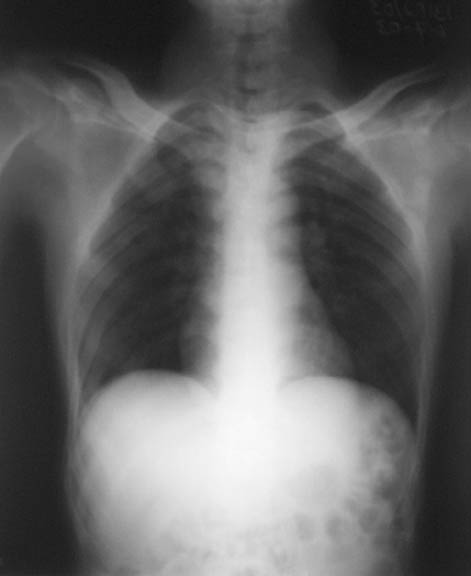

This patient,a middle aged malewas a diagnosed case of hypophosphatemic osteomalacia on treatment. Unfortunately he discontinued treatment since he was poor and also neutral phosphate was not available locally. He presented with pathological fracture of left femur and a failing neck of same femur.

We managed to get neutral phosphate, initiated medical treatment and did an antegrade SIGN nailing of left femur along with couple of screws to neck using miss a nail technique. He complained of pain of the right femur and both forearms. In OT these areas were screened using image intensifier and found that he has looser zones of all these with impending fractures. Yesterday we did a retrograde nailing of right femur usingSIGN nail. Both ulnas were stabilised usingLambrudini wires in a closed fashion. All fractures and looser zones were stabilised by closed surgery using image intensifier. It may be interesting to see the post of picture of both the hips in which one side shows an antegrade femoral SIGN nail and the other side shows a retrograde SIGN nail.